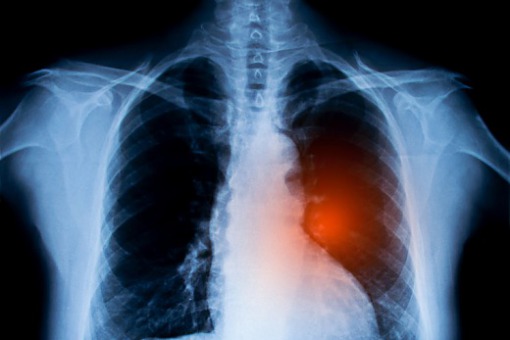

Jak wykazano w badaniu klinicznym CHRYSALIS, stosowanie amiwantamabu wiąże się z wysokim odsetkiem długotrwałych odpowiedzi na leczenie u chorych na niedrobnokomórkowego raka płuca z insercją w eksonie 20 genu EGFR, u których doszło do progresji choroby w trakcie lub po chemioterapii opartej na pochodnych platyny.

Mutacje aktywujące w genie EGFR są najczęściej występującym zaburzeniem molekularnym u chorych na niedrobnokomórkowego raka płuca. Większość z nich (85%) stanowi delecja w eksonie 20 oraz substytucja L858R w eksonie 21. Trzecim co do częstości zaburzeniem molekularnym jest insercja w eksonie 20 genu EGFR – jest to zburzenie heterogenne obejmujące ponad 100 wariantów wykrywanych w badaniu NGS. Insercje w eksonie 20 genu EGFR wykrywane są u około 4% chorych na zaawansowanego niedrobnokomórkowego raka płuca i u 4–12% chorych z obecnością mutacji w genie EGFR. Są też częściej wykrywane u osób, które nigdy nie paliły papierosów.